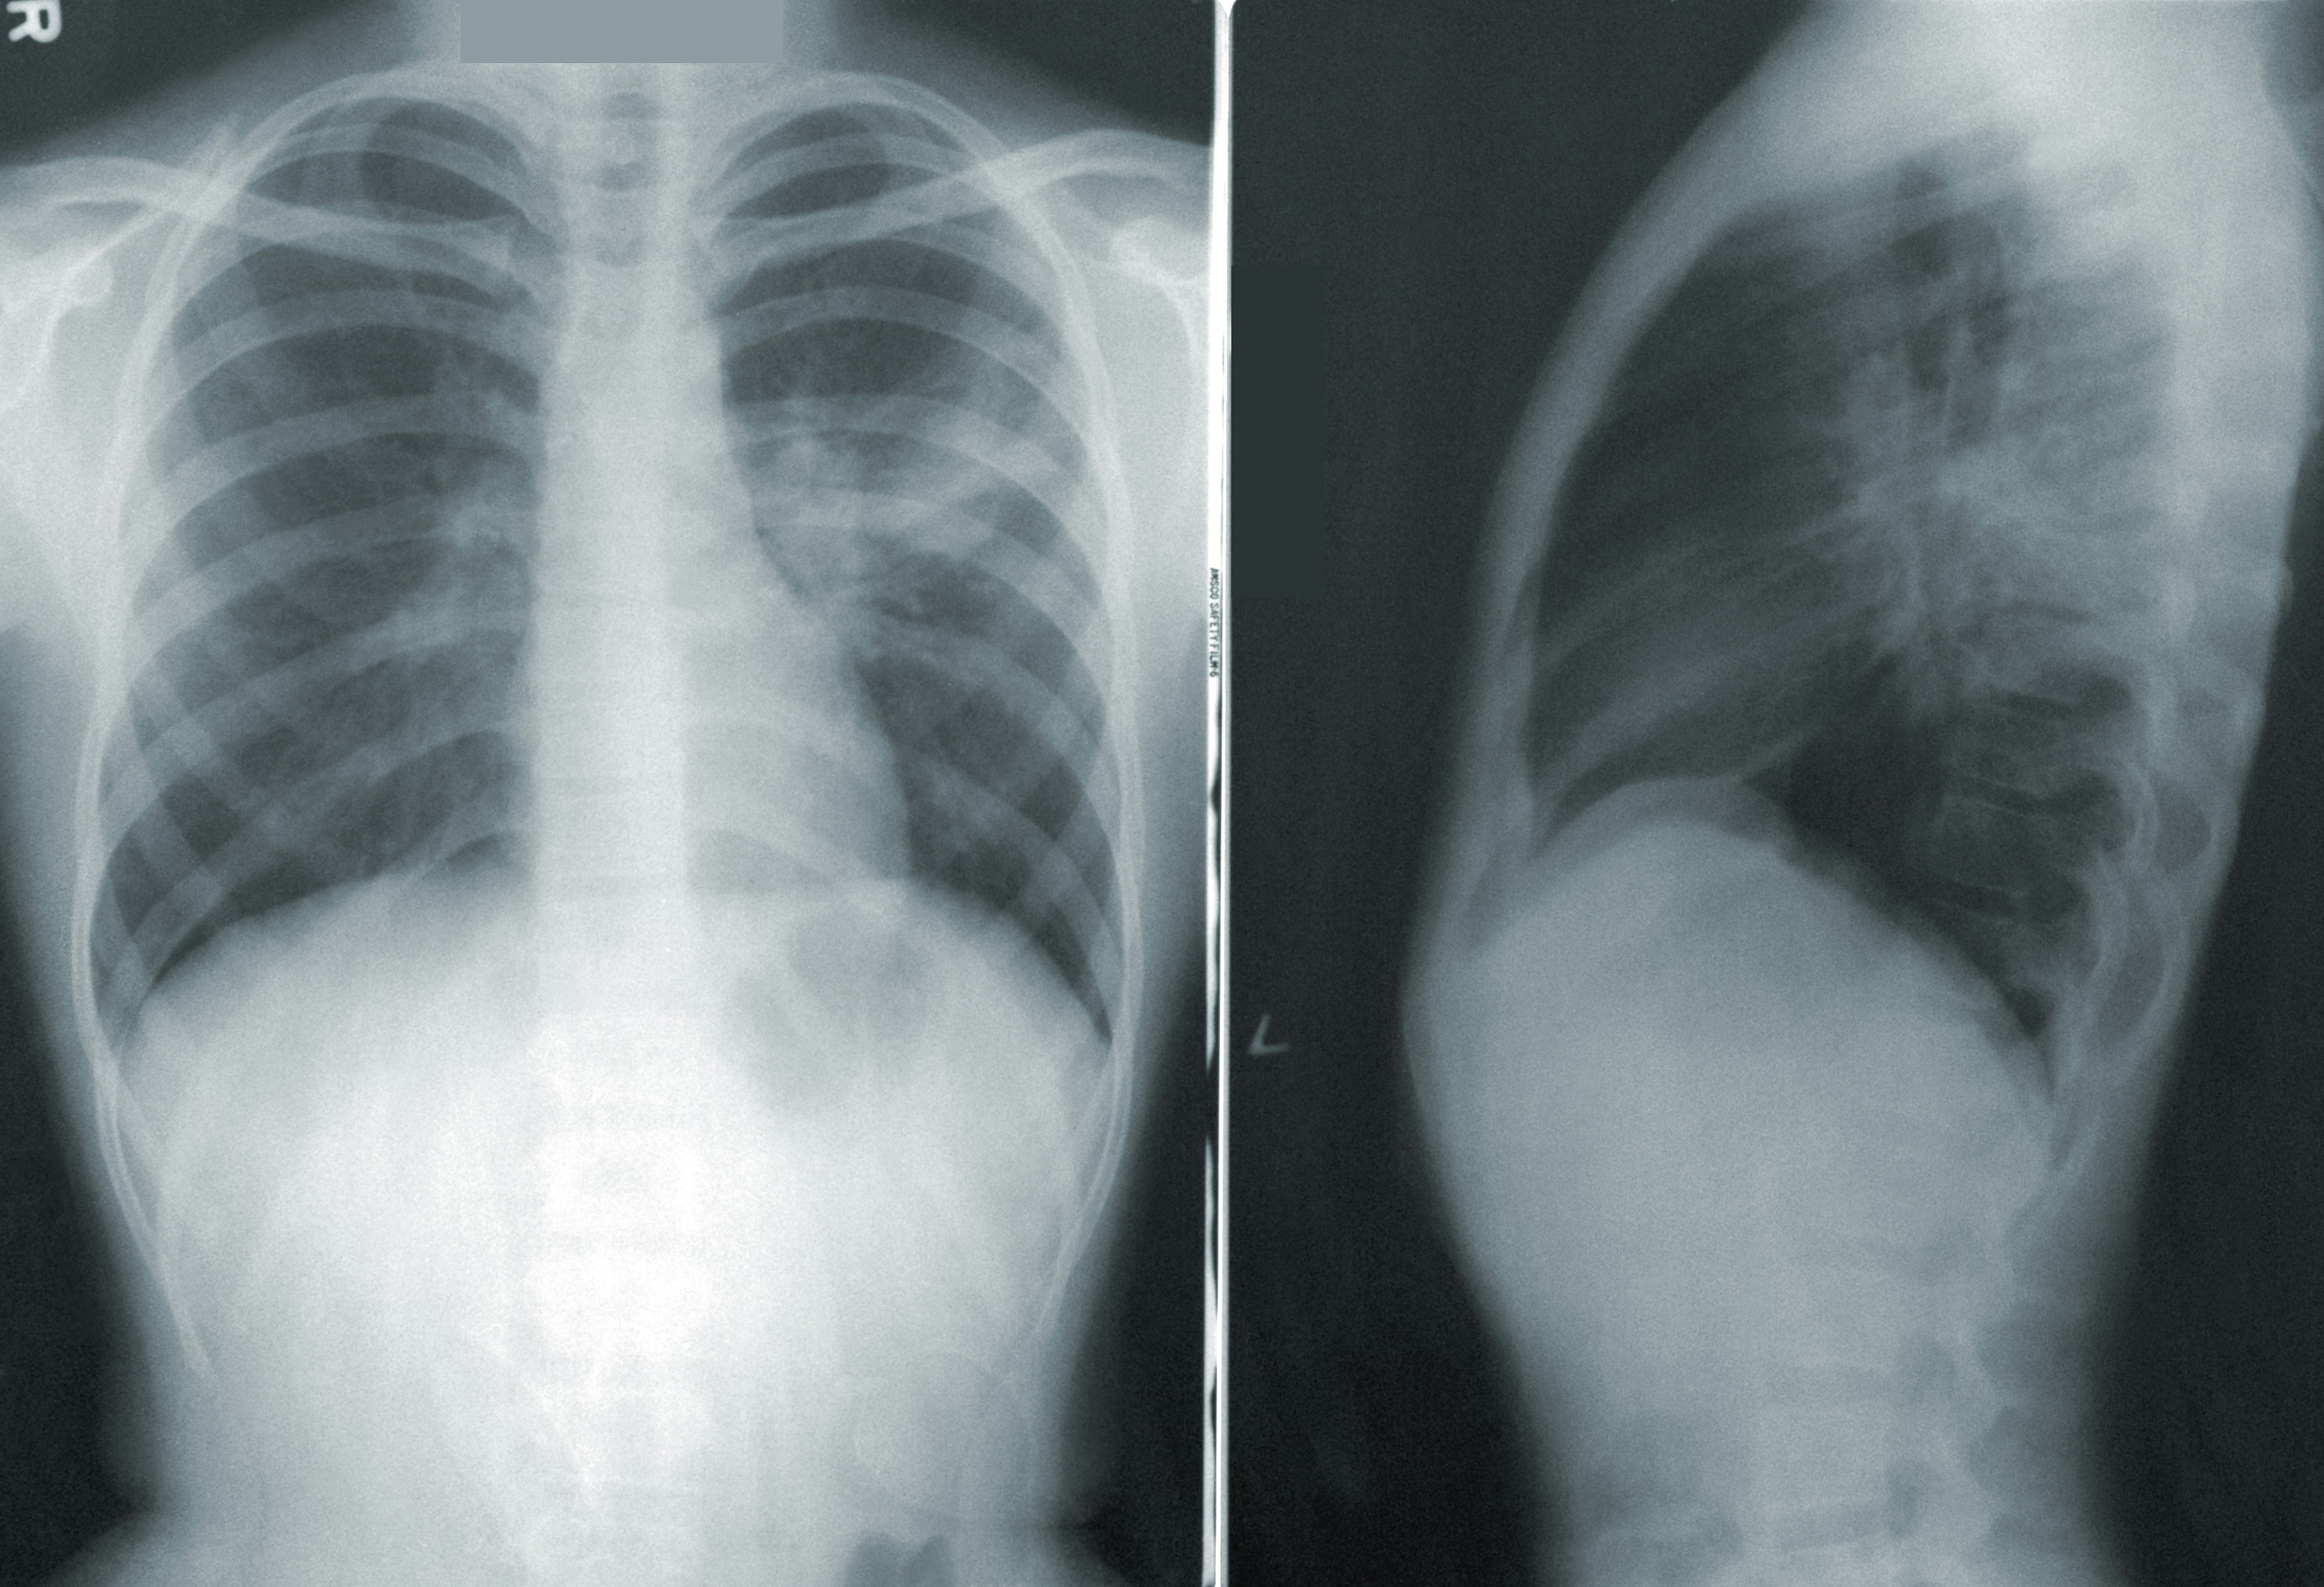

3. 폐 건강과 NAC

폐 건강을 유지하기 위해 가장 중요한 것은 염증과 점액의 적절한 조절입니다. NAC는 점액을 묽게 하고 배출을 돕는 역할을 하여, 기침과 가래를 줄여주는 데 효과적입니다. 특히 흡연자, 미세먼지 노출이 잦은 사람들에게 추천됩니다.